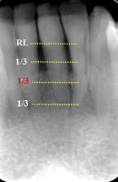

normal alveolar bone

first sign of bone loss is loss of cortication of interproximal bone

horizontal bone loss

parallel movement of alveolar crests towards the apex of the tooth

mild horizontal bone loss

blunting of alveolar crests and slight loss of height